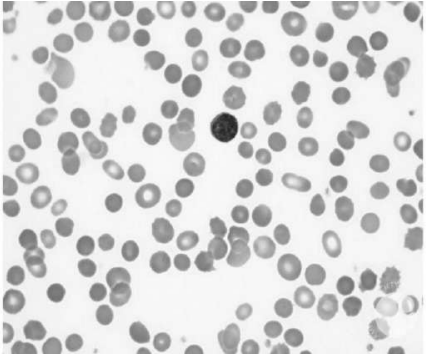

Uma paciente de 16 anos de idade é encaminhada para avaliação por apresentar anemia. Ela queixa-se de fadiga recorrente, porém os sintomas pioraram no último ano. Não faz uso de medicamentos contínuos; utiliza somente polivitamínicos. No respectivo histórico familiar, não possui quadro de anemia crônica. Informa que a irmã mais velha foi submetida a colecistectomia aos 21 anos de idade. Ao exame físico, apresenta icterícia discreta e baço palpável a 3 cm do rebordo costal esquerdo. Os exames laboratoriais mostram hemoglobina = 9.1g/dL, leucócitos = 5.600 x 109 /L, plaquetas = 188.000 x 109 /L, VCM = 106 fL, reticulócitos = 8%, bilirrubina total = 2.8 mg/dL, direta = 0.5mg/dL e desidrogenase lática = 830 UI/mL. O esfregaço sanguíneo pode ser verificado a seguir.

Disponível em:<https://imagebank.hematology.org/atlas/60308> . Acesso em: 8 jan. 2021.

Considerando esse caso clínico, a imagem apresentada e os conhecimentos médicos correlatos, julgue os itens a seguir.

A transmissão dessa condição dá-se de forma recessiva na maioria dos casos.